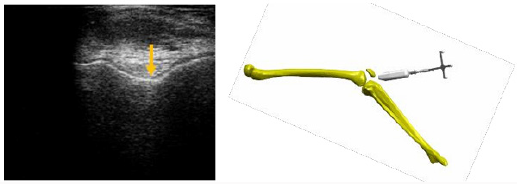

Trochlea groove, intercondylar notch and tibial tuberosity were detected from cranial to caudal. The subject was sitting in 60 degrees of knee flexion. The probe was first placed transversely above the patella and tilted from caudal to cranial until the depth reaches its maximum. The deepest point of the echogenic structure is the trochlea groove (Figure 3). Next, the probe was positioned directly under the patella. The intercondylar notch becomes visible (Figure 4). This distinctive landmark is the deepest point of femoral articulation surface. Transversally, the tibial tuberosity was localized at the proximal tibia. The high point of this land- mark is in evidence (Figure 5).